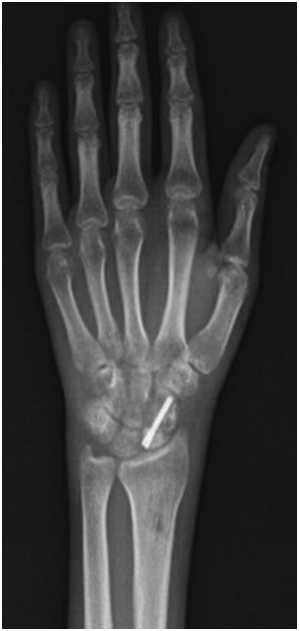

A 23-year-old male patient who was suffering from severe pain and limitation of movement on the left hand and wrist presented to our clinic. The patient’s complains were started 18 months ago. After surgical intervention for avascular necrosis 45 days ago he used casting for 30 days. After surgery the pain has turned out to be more severe and burning. On the physical examination, there was nearly complete limited range of motion on the entire movements of the left wrist, metocarpophalangeal, proximal interphalangeal, and distal interphalangeal joints. Furthermore, especially dorsal redness, thin, shiny, moist skin, increased heat and increased hair on the left hand was detected (Figure 1). There was patchy osteopaenia particularly in the peri-articular regions (Figure 2). With the diagnosis of complex regional pain syndrome type-1 calcium 1000 mg / day, cholecalciferol 800 IU/day, naproxen sodium 750 mg / day and gabapentin 1800 mg / day was started. A rehabilitation program was started including TENS, contrast bath, electrical stimulation and exercise program. After 4 weeks of treatment, the patient's pain was completely reduced. Wrist and other hand joint movements were completely turned out to be normal (Figure 3). Written consent of the patient has been obtained.

Figure 2 Patchy osteopaenia.